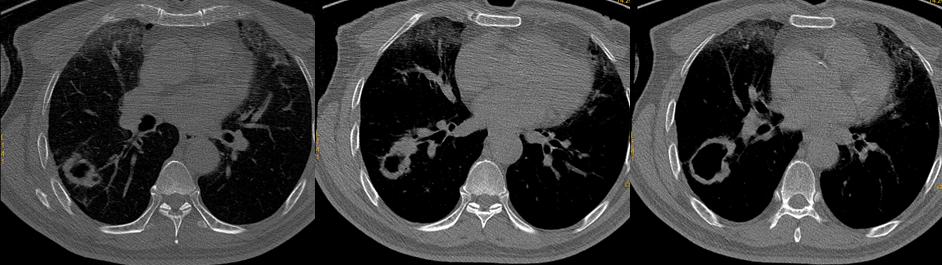

术前影像学检查(2020.7)

*CT显示右肺下叶癌性空洞性病变,纵膈无淋巴结转移。